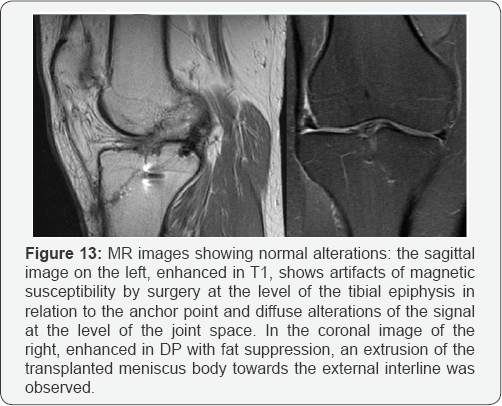

i. The presence of mild signal hyperintensity (Figure 12) and a certain degree of extrusion of the transplanted meniscus (Figure 13) should be considered normal and should be distinguished from disinsertion.